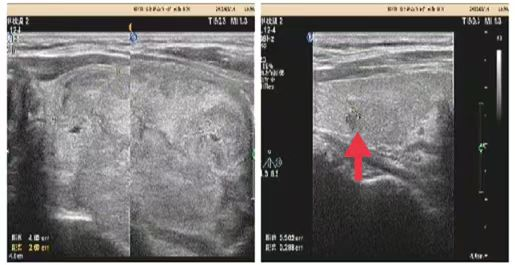

06**女士,60岁

2023年9月14日在邯郸仁泰南区体检,甲状腺彩超检查提示:甲状腺左叶形态失常,内可见大小约4.8*2.6cm等回声,边界清,内可见多个无回声,较大约0.51*0.45cm。诊断为甲状腺结节占位性病变,2023年9月16日通知客户到专科医院进一步检查。2023年9月30日跟踪回访,客户已在邯钢医院完成手术治疗。

09**女士,47岁

2023年9月22日在宜昌仁康体检部体检,甲状腺彩超检查提示:甲状腺双叶低回声结节伴部分钙化,右叶7.0*5.9mm;左叶6.4*5.7mm(TI-RADS4B级),建议进一步检查。2023年9月28日跟踪回访,客户告知在宜昌市中心医院穿刺检查诊断甲状腺乳头状癌,已完成手术。